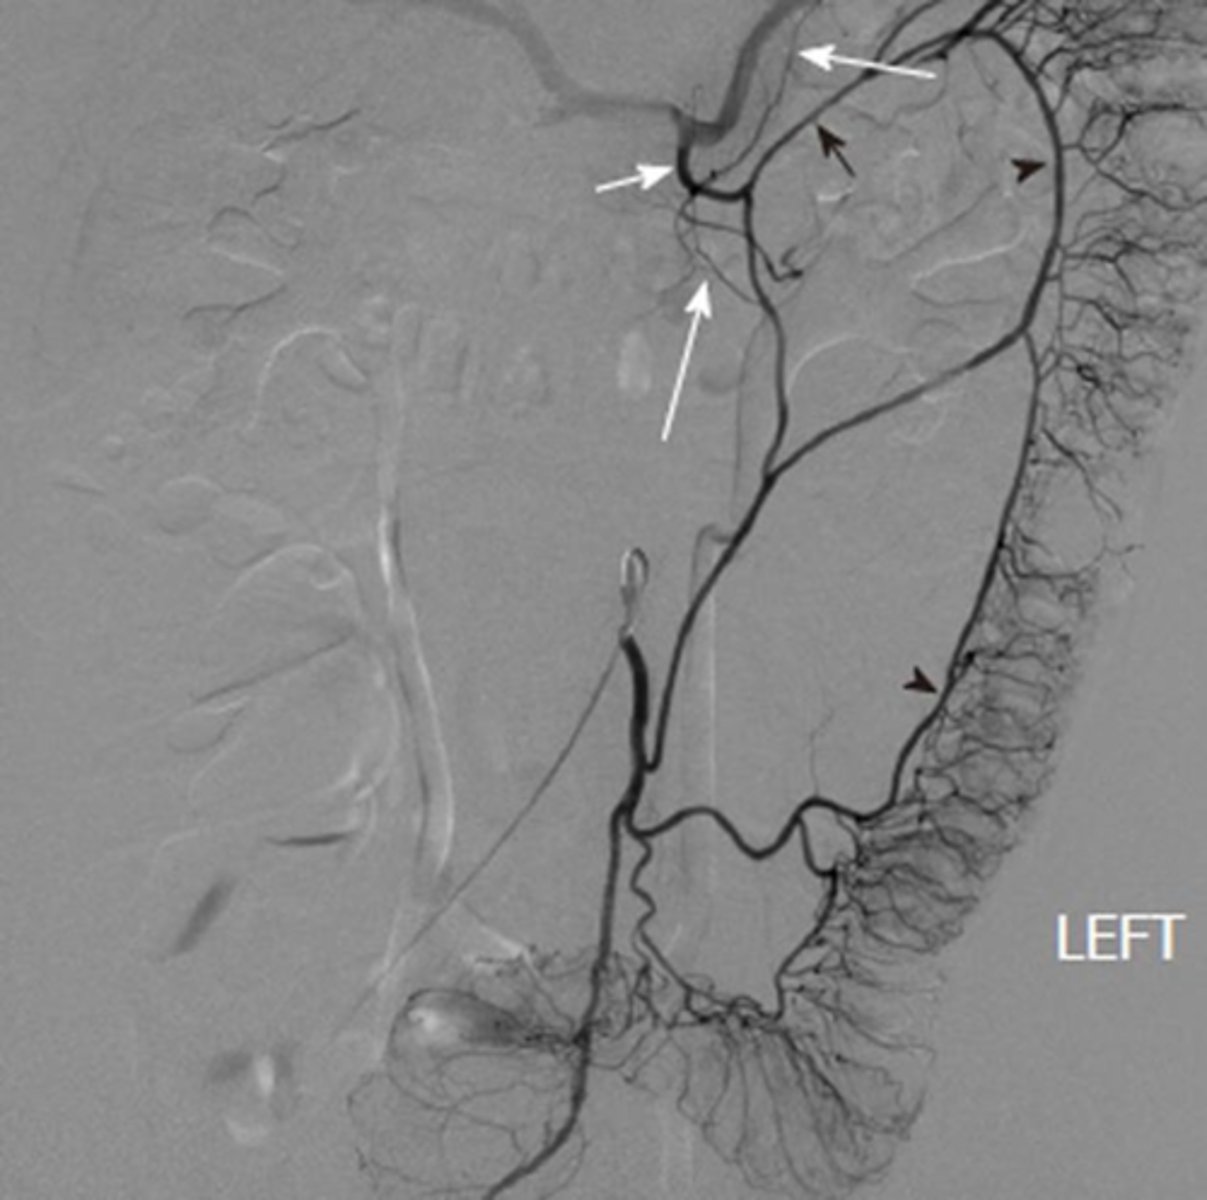

Identify pertinent anatomy in the following radiograph

knowt flashcard image